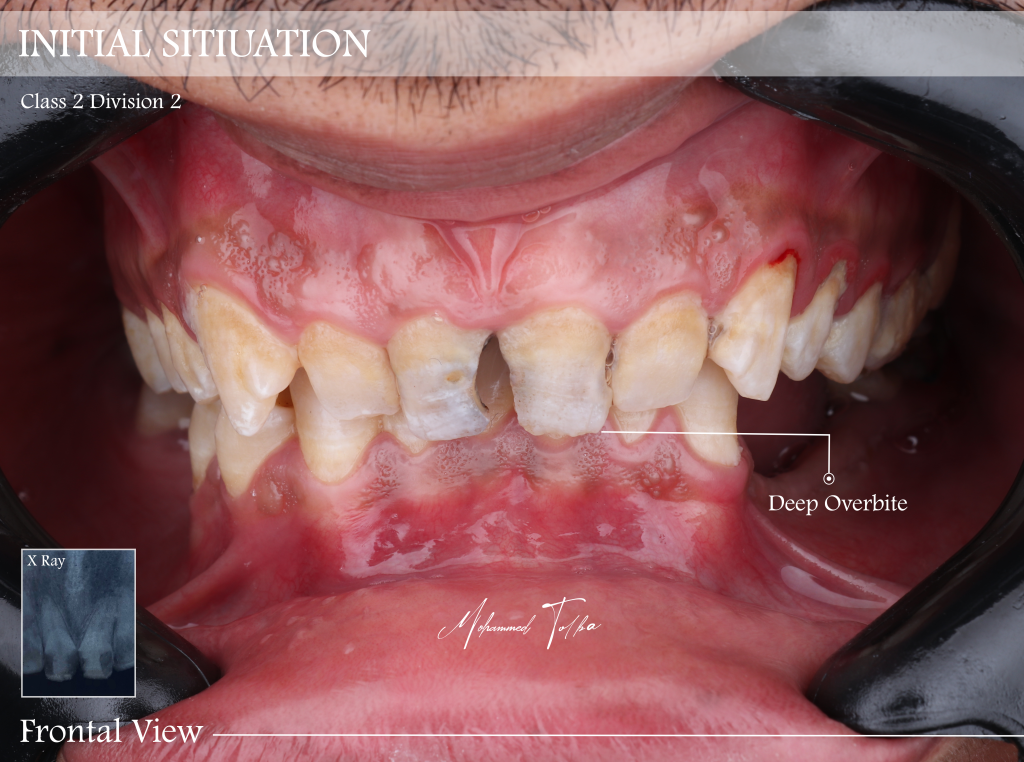

The patient initially presented with aesthetic concerns, refused ortho in this time

The patient had four anterior teeth retruded palatally, associated with a deep bite and bilateral posterior stoppers

The occlusion was maintained